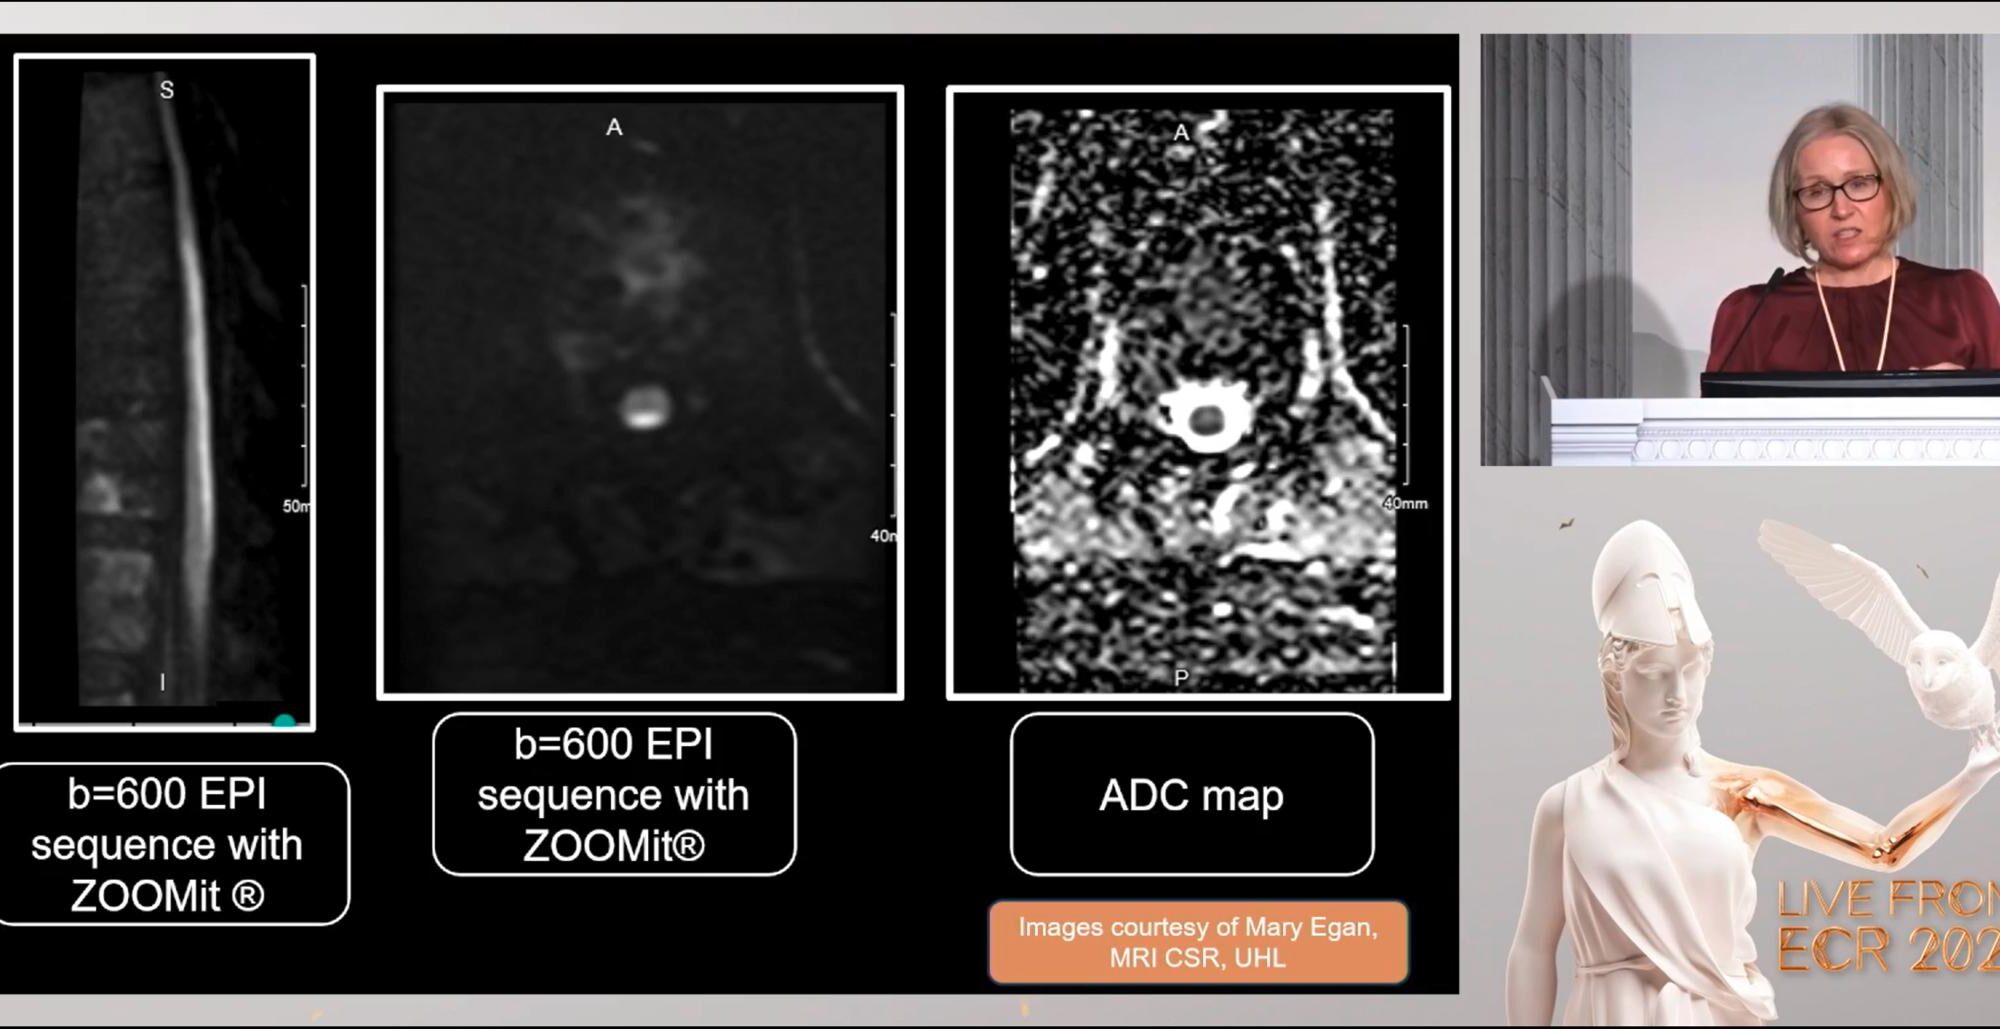

La véritable évolution récente réside dans l’intégration du deep learning au sein même de la reconstruction des séquences IRM. Les nouvelles solutions proposées par les constructeurs permettent d’agir directement sur le rapport signal/bruit et sur la vitesse d’acquisition. Une première application consiste à améliorer les images sans allonger le temps de scan. « Nous pouvons nettoyer une image sans ajouter de temps à notre